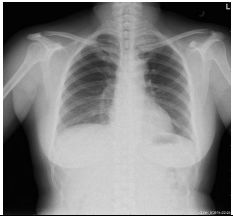

1. A 39-year-old man had this chest X-ray on his health exam. No any clinical symptoms.